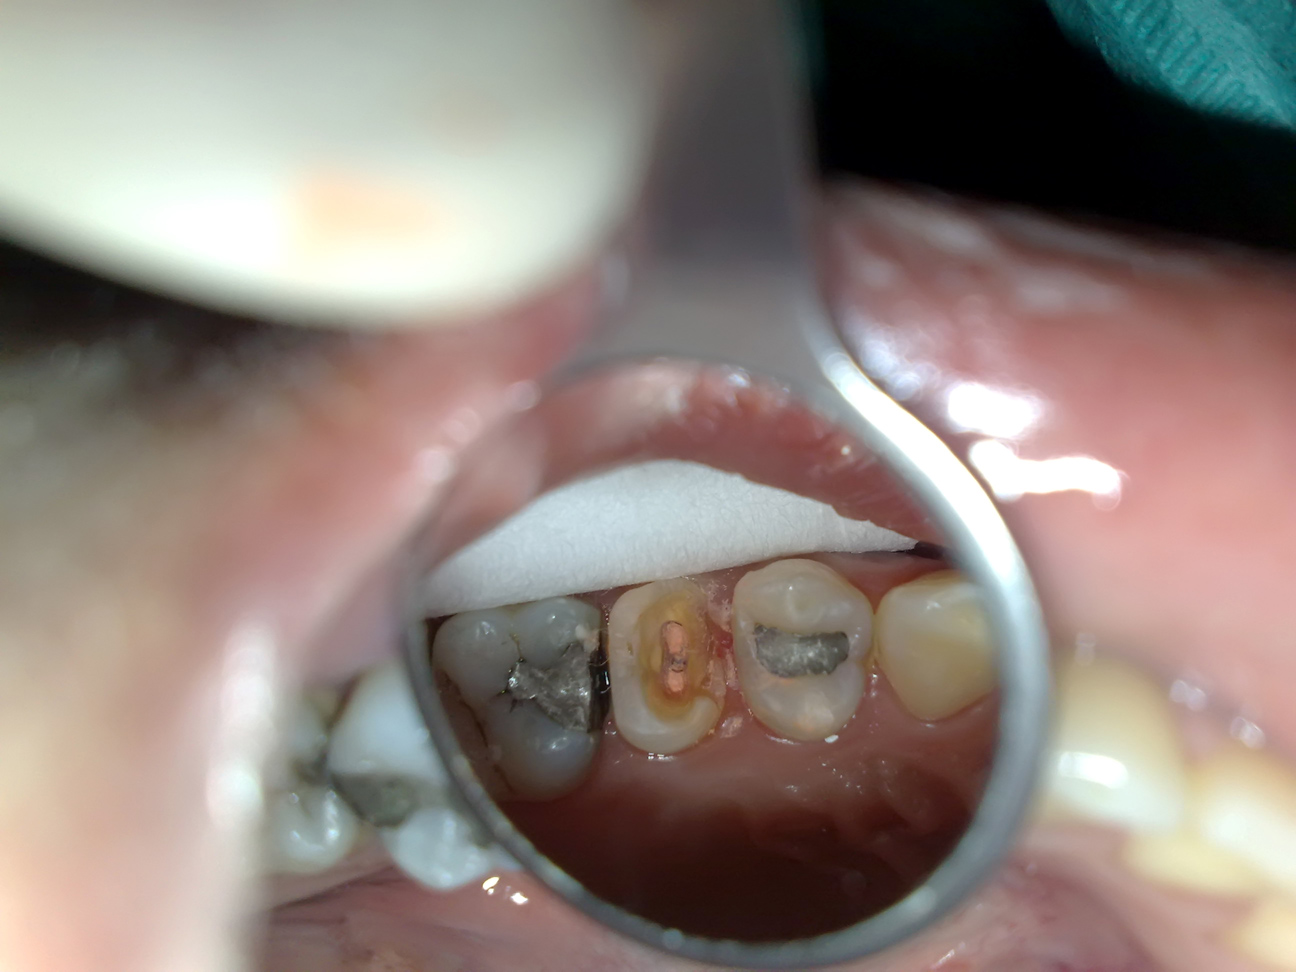

Endodontic treatment on upper left first molar with broken mesial and distal wall